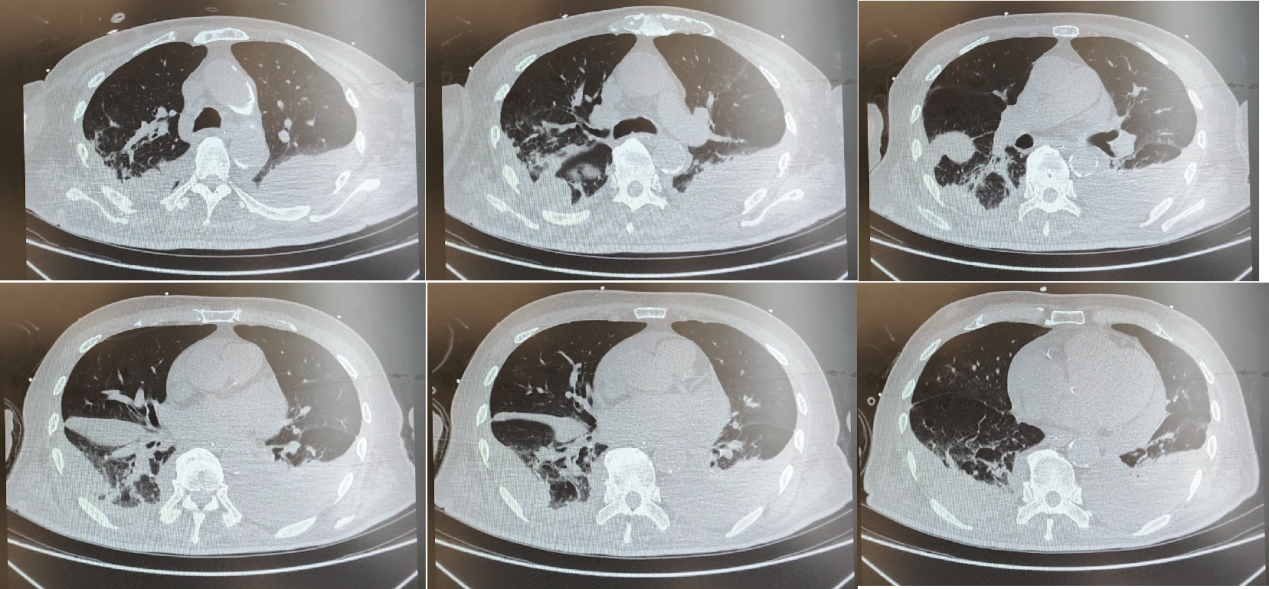

9月25日,痰培养检出碳青霉烯耐药肺炎克雷伯菌(CRKP)和碳青霉烯耐药铜绿假单胞菌(CRPA)。9月26日,患者CRP(66.43 mg/L)、ESR(49 mm/h)迅速上升;复查胸片示:双肺炎症,较前进展。考虑当前抗菌方案对CRKP及CRPA抗菌力度不足,遂根据IDSA 2023指南[1],优化抗感染方案为:依拉环素(50 mg,ivdrip,q12h,输注60min以上)+头孢哌酮/舒巴坦(3 g,ivdrip,q6h,维持3h)+头孢他啶/阿维巴坦(2.5 g,ivdrip,q8h,维持3h)。

10月5日,患者炎症得到有效控制,血常规示患者CRP(1.79 mg/L)及ESR(13 mm/h)均显著下降;胸片较前缓解。遂进行降阶梯治疗,调整抗感染方案为:头孢哌酮/舒巴坦+米诺环素+头孢他啶/阿维巴坦。10月10日,复查胸片,肺部炎症面积较前减少,氧合指数较前好转,炎症指标较前降低。应用以上方案抗感染治疗2周后患者症状好转。

△院内治疗过程中患者胸片变化(09-26、10-05、10-10)